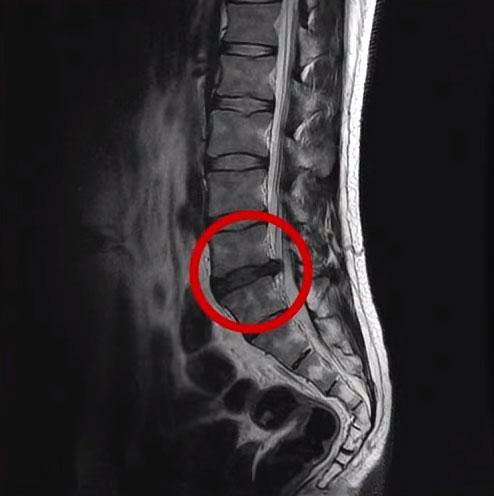

대부분의 만성허리통증 환자는 퇴행성허리디스크를 갖고 있는 경우가 많습니다. 그래서 허리가 장기간 아팠던 분들 경우 한 번도 MRI를 찍어보지 않으셨다면, 이런 분들에게는 MRI 검사가 큰 의미가 있습니다. 퇴행성허리디스크에서 ‘퇴행’이란 늙고, 약해지고, 기능이 떨어졌다는 것입니다. 이렇게 퇴행성허리디스크가 있는 분들 경우에는 건강한 사람들에게는 아무 것도 아닌 일상적인 생활들이 무리가 될 수 있으며, 특히 1시간 이상 오래 앉아 있거나 1시간 이상 운전하는 것, 그밖에 등산이나 골프 등과 같이 허리에 무리가 되는 활동이나 운동 등은 통증을 더 심하게 만들 수 있습니다.